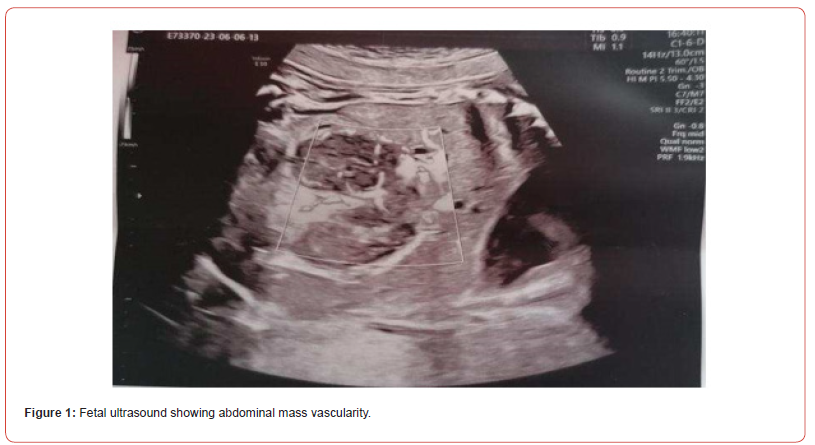

A 37 years-old pregnant woman, gravida 2 para 2, was referred to our hospital by her Gynaecologist for fetal abdominal and pericardial effusion at 35 4/7 weeks. Up to this point her pregnancy was eventful for a diagnosis of gestational diabetes with unremarkable ultrasounds up until the third trimester when the fetal stomach could not be visualized. Fetal growth was at the highest percentiles and amniotic fluid levels were normal. Our ultrasound showed subcutaneous oedema mostly at the abdomen (10 mm) and prefrontal space (8.5 mm), mild intra-abdominal fluid (5.4 mm) and a tubular abdominal mass moderatly vascularized with Color-Doppler with a disomogeneous echogenicity similar to the echogenicity of a clot with no peristaltic movements (Figure1,2). Fetal stomach cound not be visualized and amniotic fluid levels were normal. The ultrasound also showed reduced active fetal movements. Given the initial signs of fetal distress and the accomplished gestational age, it was decided to expedite the delivery via C- section. A female fetus was delivered, with meconium-stained amniotic fluid grade 1. In the delivery room she was ventilated due to bradycardia and apnea and subsequently intubated for the persistence of apnea. Apgar score was 3-6-7 respectively at 1’, 5’ and 10’ minute of life. Cord arterial blood gas showed anemia with 20% haematocrit and normal acid/base status. The birth weight was 2800 gr (84th centile). The baby persisted hypotonic, hyporeactive, pale, presented diffuse subcutaneous oedema and firm violaceous diffuse (face, thorax, limbs) cutaneous lesions (papules and nodules) suspicious for cutaneous metastasis (blueberry muffin baby). Palpation of the abdomen revealed a soft, non-tender, middle-abdominal mass and splenomegaly. She was then transferred to the NICU and underwent an urgent abdominal ultrasound showing: a diffusely hypoechoic voluminous mass (2,2 cm thickness) in the pancreatic space with echoic areas in its context and marked vascularization by mesenteric vessels without vessel compression. Splenomegaly with bipolar lenght of 7,4 cm with heterogeneous echotexture and hypoechoic triangularshaped areas in the subcapsular space. Transfontanellar Cerebral Ultrasound and Echocardiography Showed No Alterations.